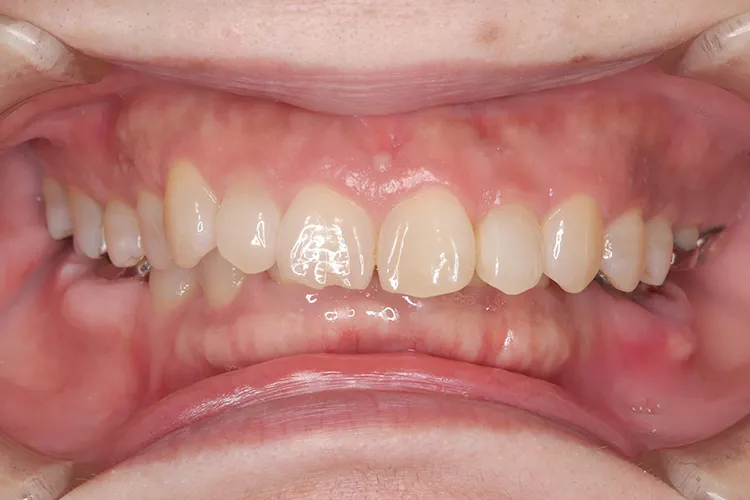

治療前

治療後

レントゲン画像

治療内容

前歯の古いブリッジが脱離し、土台となっていた3本の歯も傷みがはげしく再度のブリッジ治療が不可能な状態でした。前歯ということで欠損を放置できないため、抜歯と同時にインプラントを3本埋入し即日で仮歯までいれました。治療期間中、見た目を気にすることなくオペから4ヶ月で最終のジルコニア4本ブリッジを装着し治療完了しました。抜歯即時埋入は術後の痛みもほとんどなく、治療期間の短縮や患者様の負担軽減などメリットの大きい治療法です。